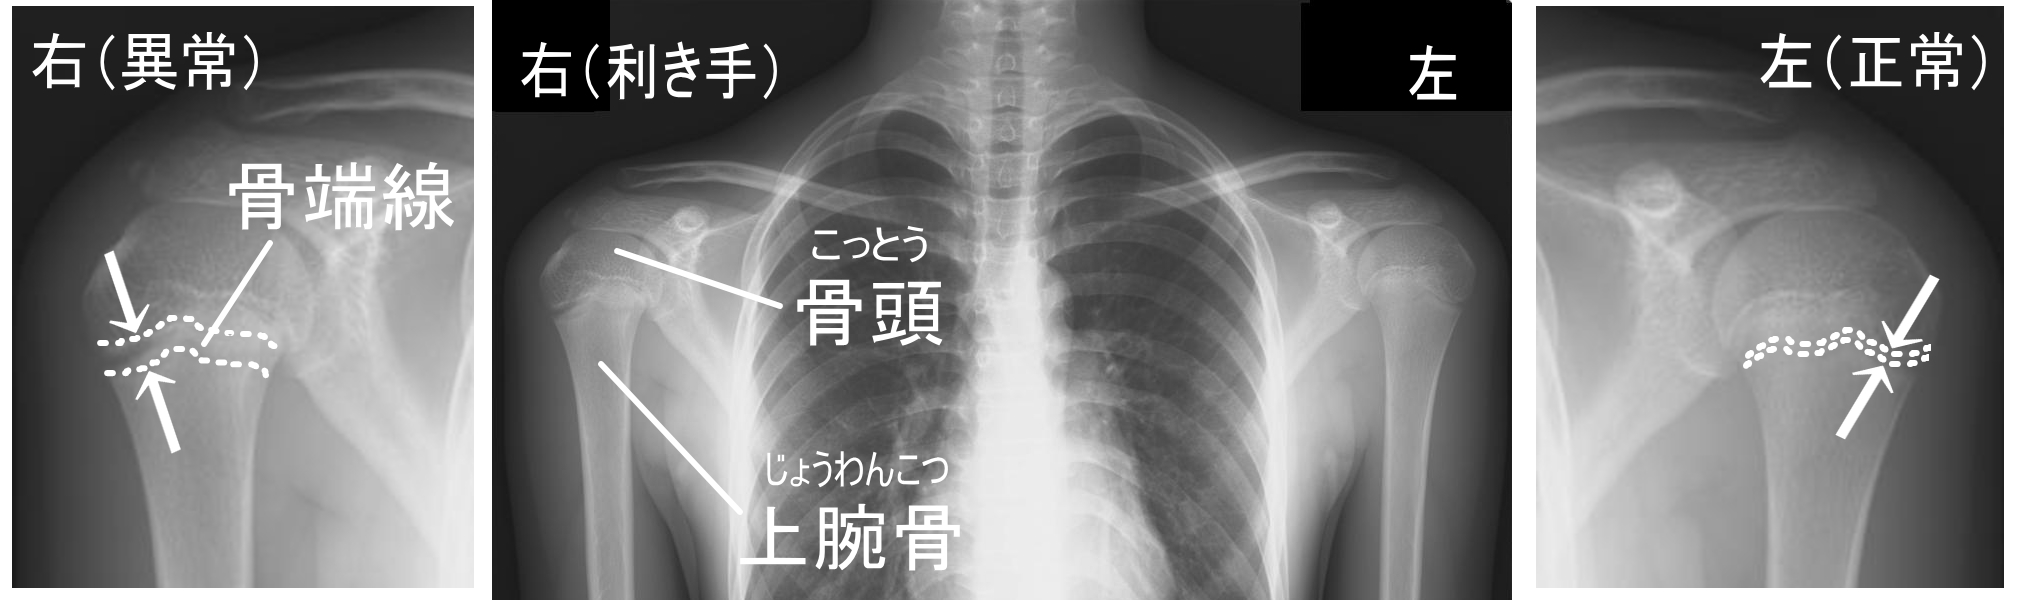

リトルリーガーズショルダー(上腕骨骨端線離解)

骨端線(成長軟骨)とは・・・

骨の端にあり、軟骨が骨にかわっていく境目の部分のことです。

この骨端線があるうちは成長をしていき、成長と共に消失していきます。

主に成長期(小中高生)の野球肩のことを指し、上腕骨上端部の成長軟骨の損傷のことです。

投げる動作時に成長軟骨へ負荷がかかり離解し損傷し痛みが発生します。

投げる際は勿論ですが、日常生活においても痛みを感じることもあり、

子供の野球人生を左右してしまうこともあるので注意が必要となります。